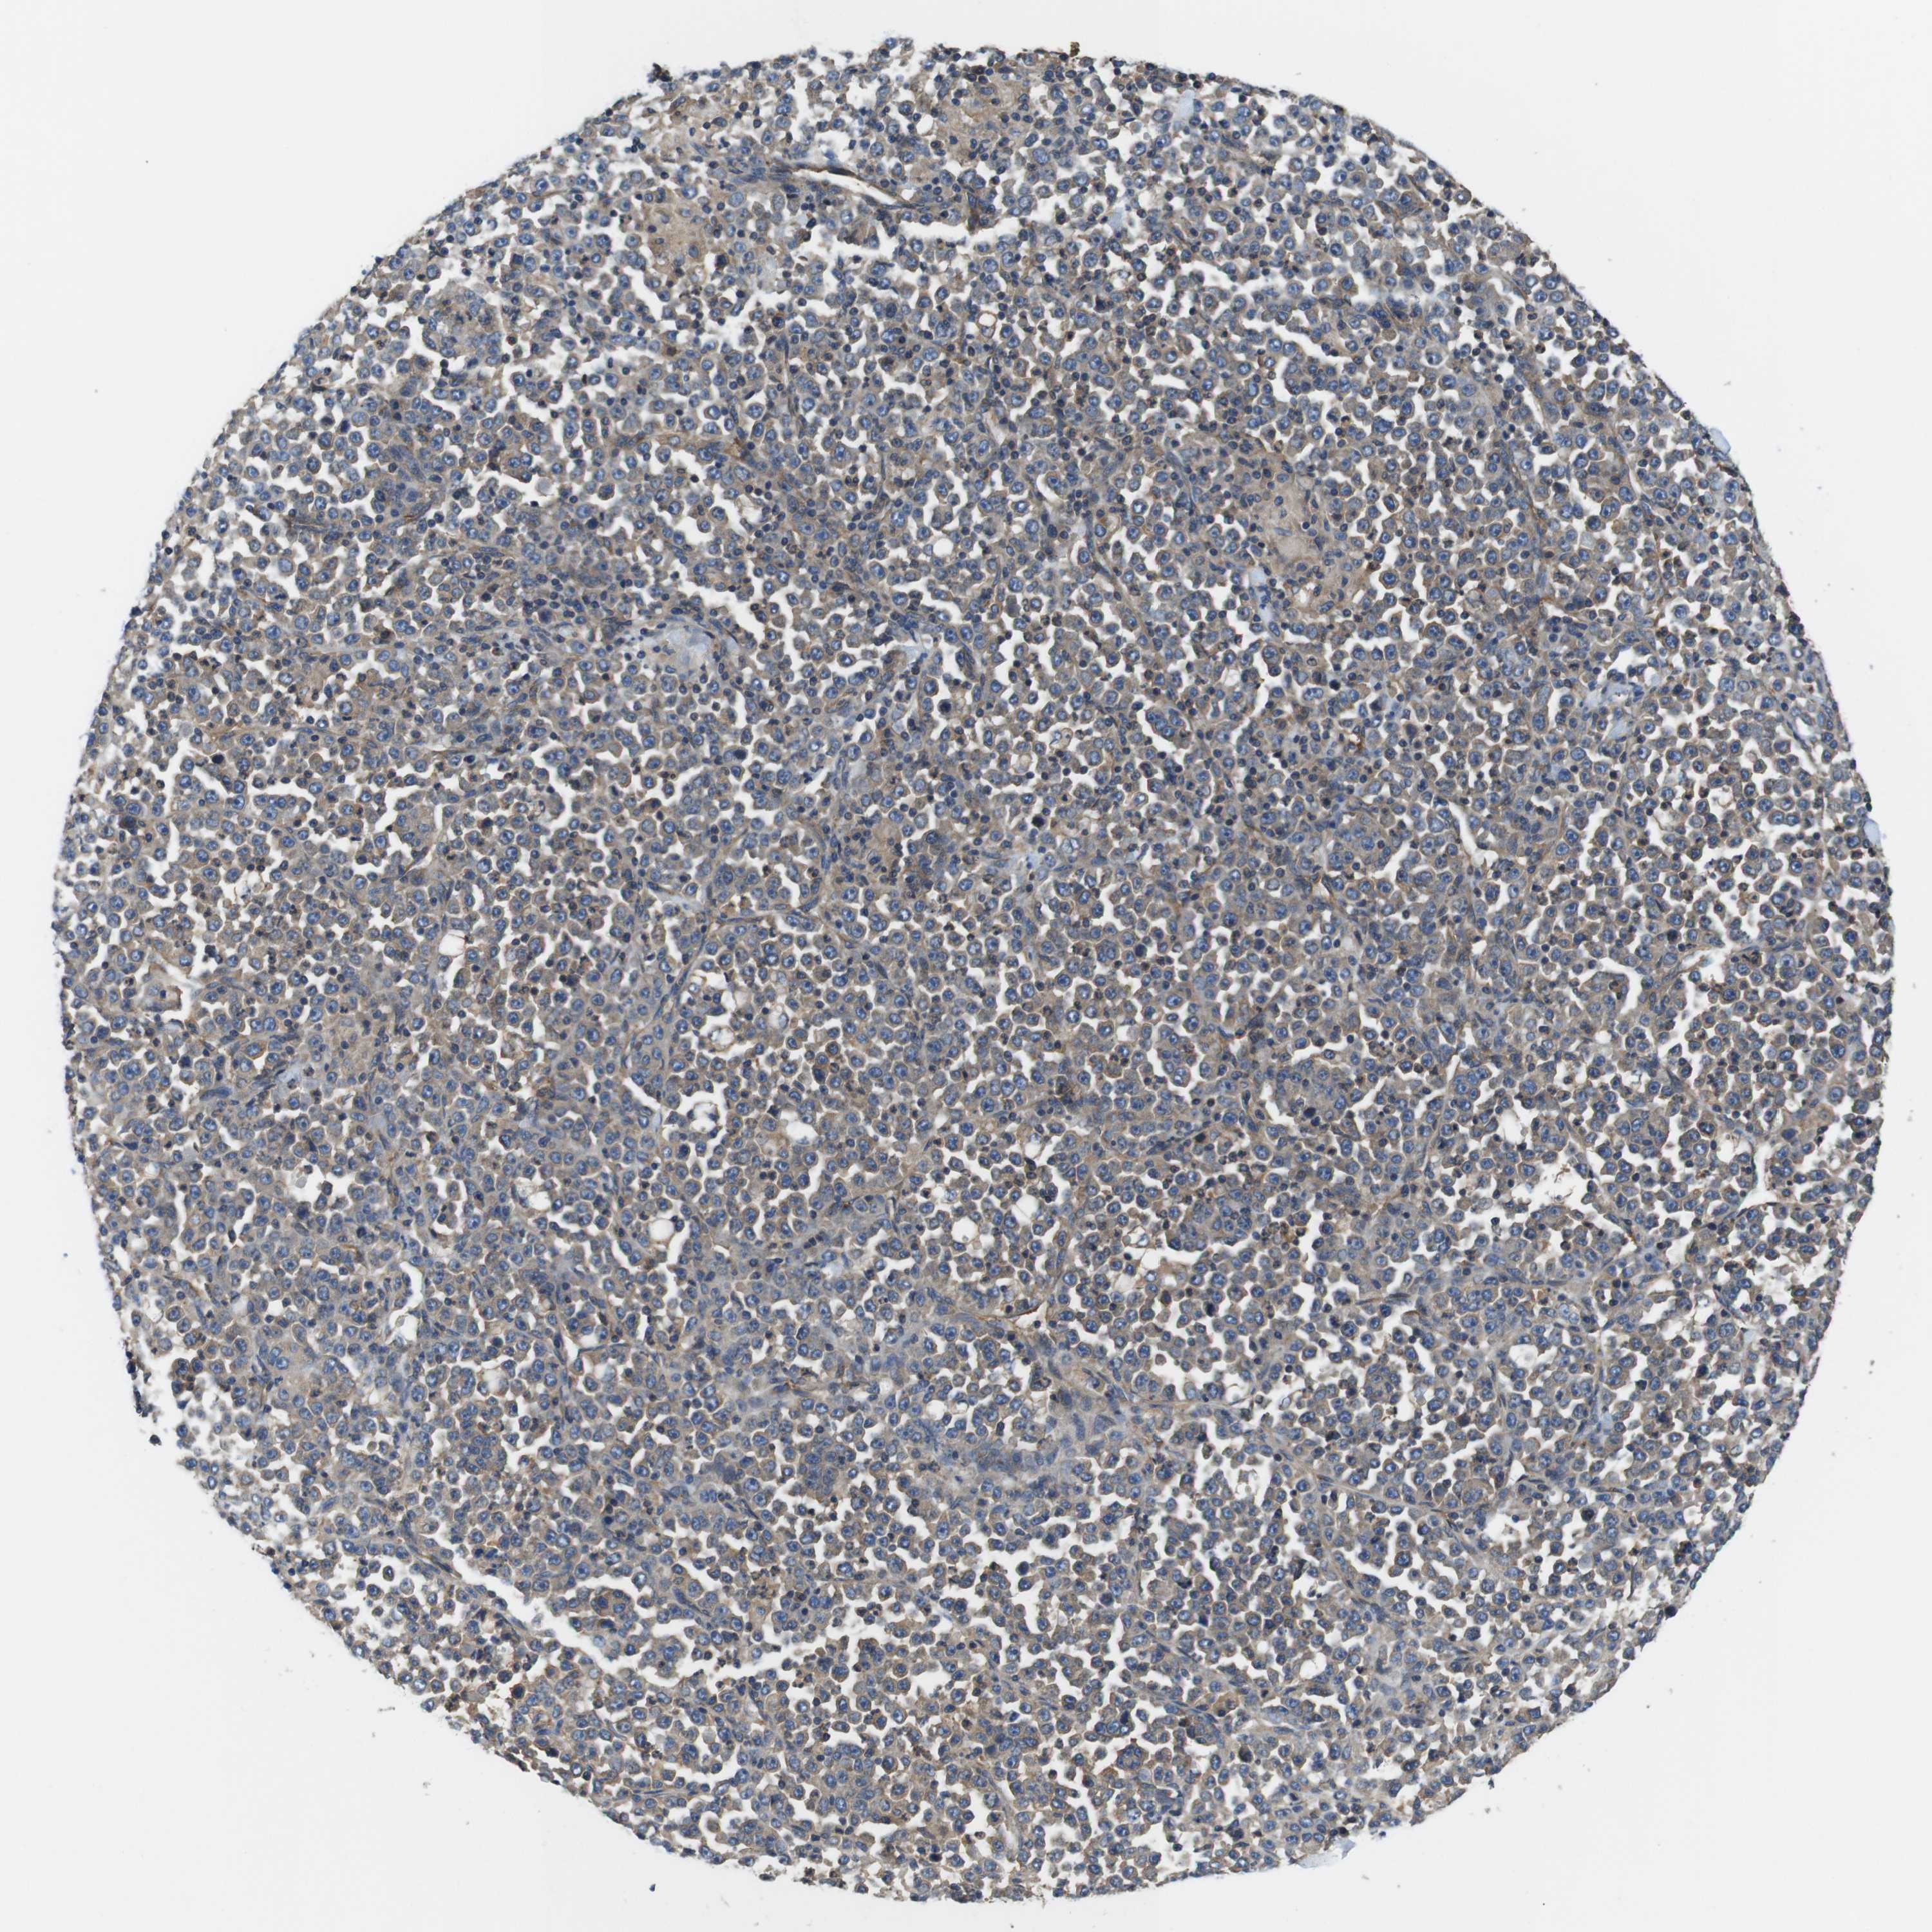

STOMACH CANCER - Protein expressioni

A mouse-over function shows sample information and annotation data. Click on an image to view it in a full screen mode. Samples can be filtered based on level of antibody staining by selecting one or several of the following categories: high, medium, low and not detected. The assay and annotation is described here.

Note that samples used for immunohistochemistry by the Human Protein Atlas do not correspond to samples in the TCGA dataset.

Antibody stainingi

Antibody staining in the annotated cell types in the current human tissue is reported as not detected, low, medium, or high, based on conventional immunohistochemistry profiling in selected tissues. This score is based on the combination of the staining intensity and fraction of stained cells.

Each image is clickable and will lead to virtual microscopy that enables deeper exploration of all samples and also displays staining intensity scores, fraction scores and subcellular localization as well as patient and tissue information for each sample.

Antibody CAB009108

Adenocarcinoma, NOS

Adenocarcinoma, High grade